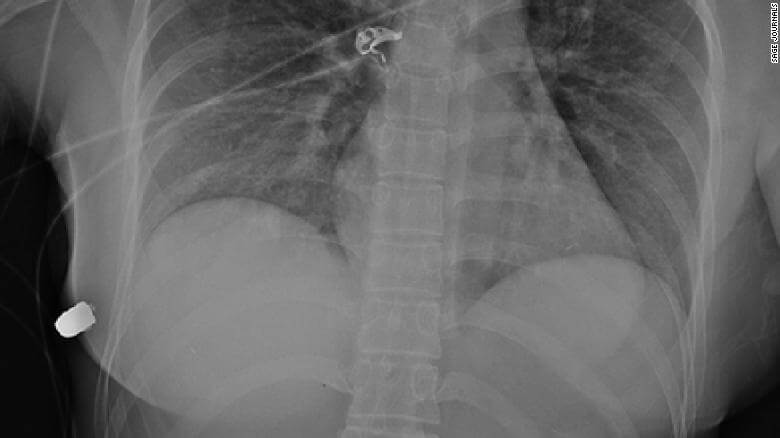

Рентгеновский снимок выжившей женщины от пулевого ранения

Входное пулевое ранение было на левой стороне груди, но перелом ребра был на правой стороне. Пуля сначала вошла в кожу с левой стороны, а затем срикошетила через грудину в правую грудь и сломала ей ребро с правой стороны. Имплантат вызвал изменение траектории полета пули,

заявил врач

Медики обнаружили твердый, похожий на пулю предмет в правой нижней передней грудной стенке ниже правой груди. С помощью рентгена определили, что это была пуля, а так же увидели сломанное ребро и пузырьки воздуха в левой груди, после чего и пришли к выводу, что пуля прошла от левой груди к правой грудной стенке.

В итоге женщина получила повреждение имплантатов и сломанное ребро. Других повреждений при исследовании выявлено не было. Как мы знаем, с левой стороны у человека находится сердце и легкие. Если бы пуля не изменила траекторию движения — спасти женщину скорее всего бы не удалось.